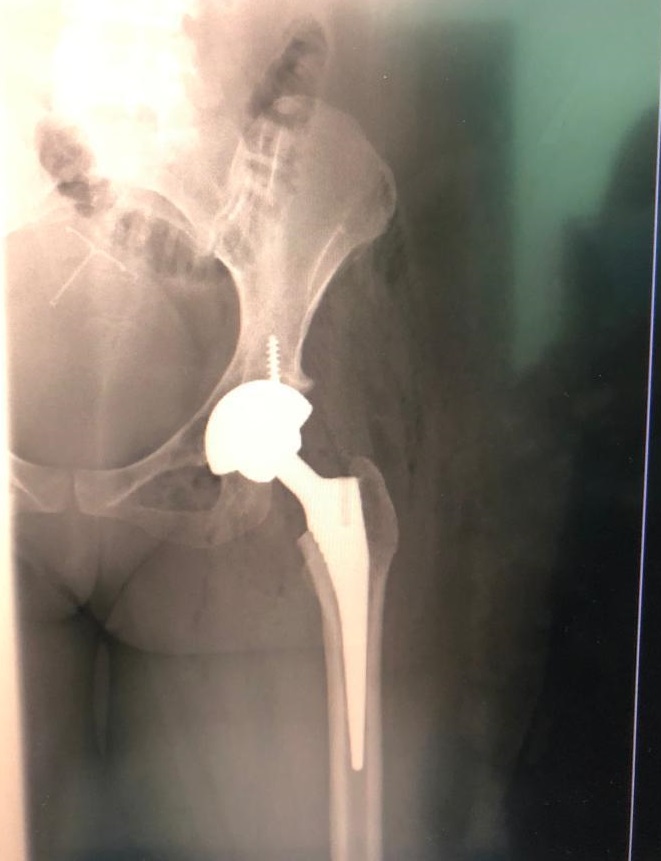

Patient 23

38 year old with avascular necrosis of the hip

Ceramic on poly articulation